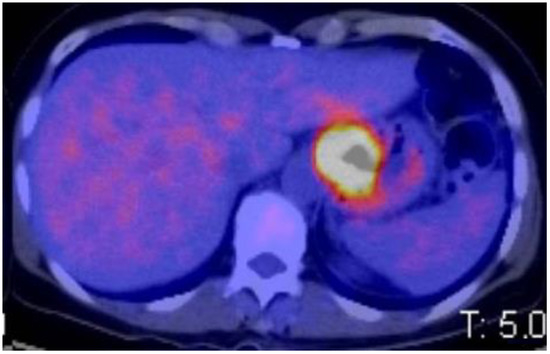

2.4. PET-CT Staging

2.5. Follow Up